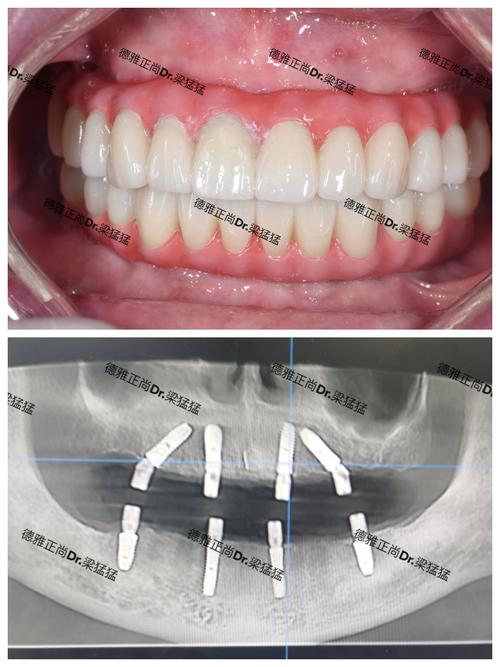

经过骨增量处理后,种植牙流程通常包括:术前检查(CBCT评估骨量、血常规等)、骨增量手术(如需要)、种植体植入(骨愈合期3-6个月)、基台安装、牙冠制作与戴牙,整个过程需3-6个月,具体时间取决于骨愈合速度和个体差异。